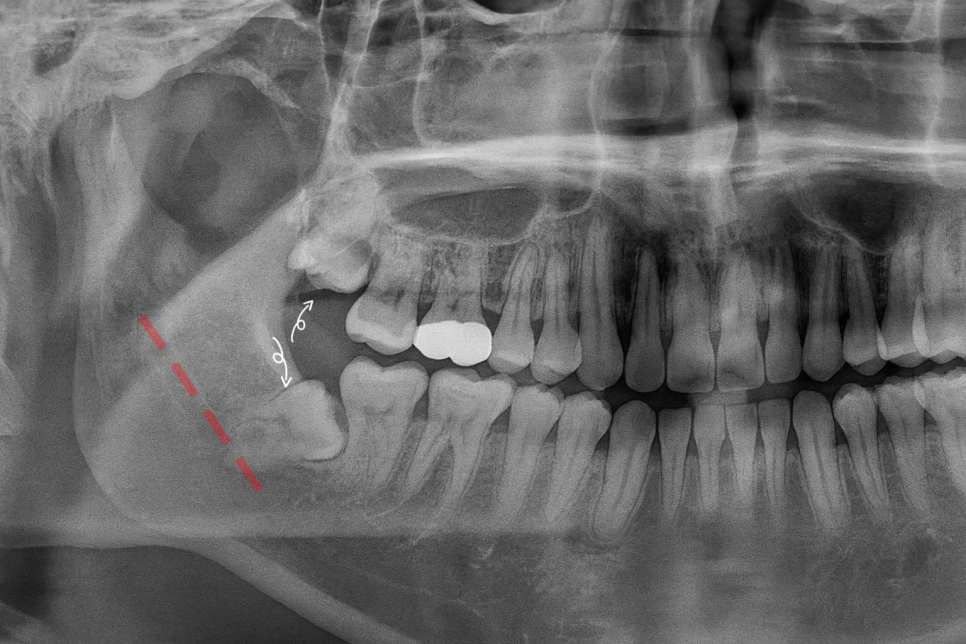

영등포동 치과 에서 준비한 사진을 보시면

하악공에서 하악관 속으로 들어가 악골 내를 주행하는 하치조 신경이 관찰됩니다.

지치가 잇몸뼈 내에 매복되어 있거나

위치가 불량할 경우에 거리적으로 가까워 문제가 되곤 합니다.

하치조 신경이라는 구조와 가까워지게 되면

진료 과정에서 필요한 거리를 충분히 확보할 수 없습니다.

그럼 구조 손상으로 이어질 수 있는데

감각 이상 문제를 야기할 수 있어 주의를 요해야 됩니다.

대개 일반적으로 파노라마 사진을 찍어 확인하는데,

하치조 신경 본간은 X선 사진에

하악관이 찍히므로 주행을 파악할 수 있으나,

구치지, 절치지는 X선에 찍히지 않으며

분지 직후에는 비교적 굵기 때문에 악골 내

영향을 미칠 수 있는 치료 시에

구조를 정확하게 파악할 필요가 있습니다.

그래서 삼차원적인 자료인 CBCT를 함께 찍어

세밀하게 관찰을 진행하게 되죠.

제가 준비한 파노라마 사진을 보시면

우측 위아래 모두 지치가 매복되어 있습니다.

상악은 비교적 곧게 올라오고 있었으나,

하악은 수평으로 매복된 양상이 관찰되고 있습니다.

둘 다 치조골 속에 묻혀 있기 때문에

잇몸을 절개하여 외과적 발치를 진행해야 된다는 점을 동일하나,

매복된 양상이 다르기 때문에 하악의 경우에는

더욱 세밀한 관찰이 필요하다 사료되며,

필요시 치아를 여러 조각으로 분할하여

꺼내는 방식을 택하여 될 수 있습니다.

Panorama에서 하치조 신경관과 중첩되어 있는 듯한

모습이 관찰되어 CBCT를 통해 추가로 체크해 보겠습니다.

사진을 보시면 지치 하방으로 주행하고 있으며

거리가 매우 가깝다 판단됩니다.

다만, 맞닿아 있거나 누르고 있는 케이스는 아니라

진료에 필요한 최소한의 거리는 확보되는 상태죠.

이런 경우 통상적으로 분할하여 뽑아주는

방식을 택하게 됩니다.